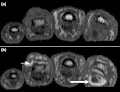

Approximately 25–70% of PsA patients have inflammation of the axial skeleton.[12] There are also post inflammatory changes.[1] Axial pain can occur in the area of the sacrum (the lower back, above the tailbone),[7] as a result of sacroiliitis or spondylitis, which is present in 40% of cases. The inflammatory pain in the axial skeleton is worse in the early hours of the day.[1] The pain is not relieved by resting, but rather by movement.[1] The pain may be located in only part of the spine or sacroiliac joints, and may radiate to the legs down to the level of the back of the knee.[1] It may be on both sides or only one side. There may also be stiffness and reduction of mobility in the spine. There are no symptoms in 20% of people with axial involvement.[1] Over time, the spine may undergo ankylosis.[1]